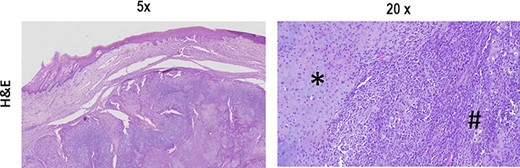

The typical biphasic pattern of MCS, composed of islands of cartilage (*) admixed with poorly differentiated small round cells with scant cytoplasm (#). H&E stain.

Diagnosis of MCS can only be established by histopathological examination, characterized by a biphasic pattern, with a sheet-like or patternless proliferation of small differentiated spindle or round cells surrounding discrete nodules of differentiated hyaline cartilage [3].